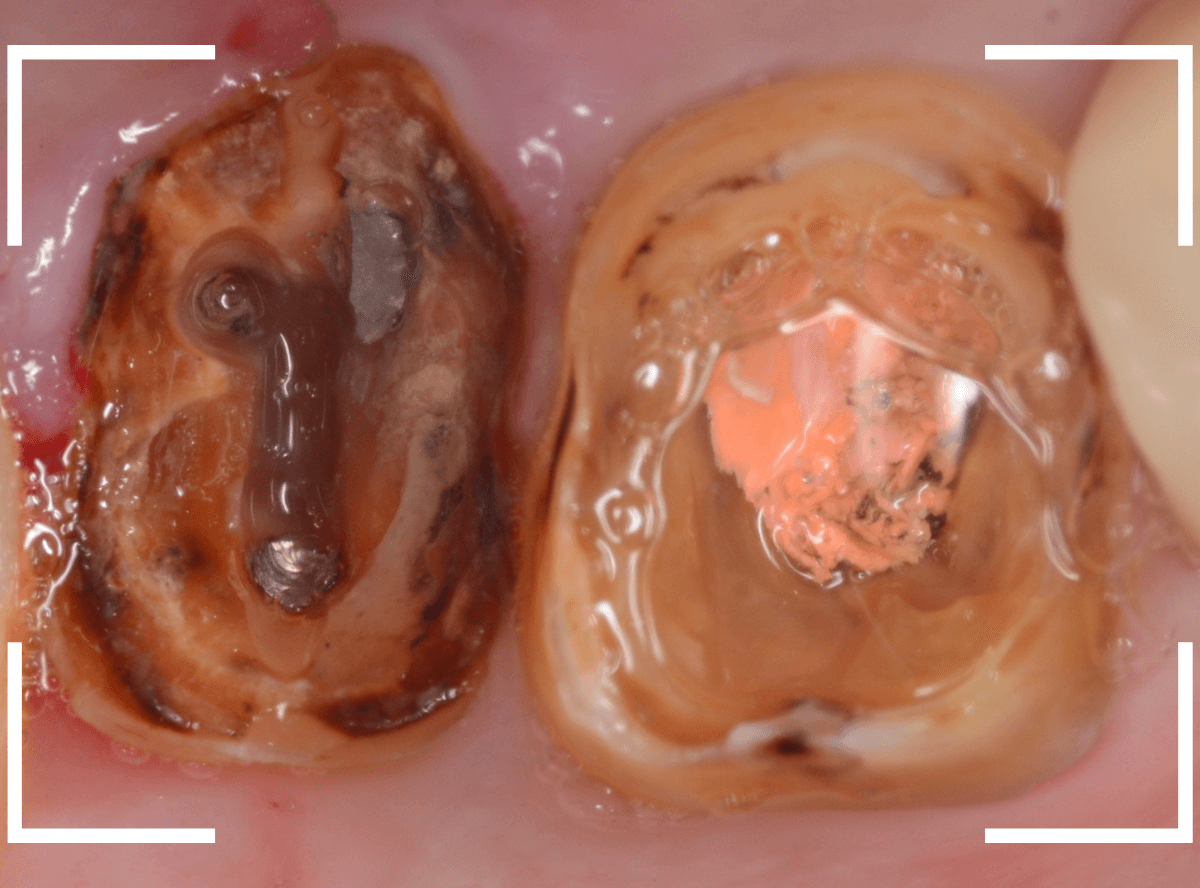

次は左側のメタルコアを除去します。

メタルコアをある程度除去したところです。

予想したとおり、中は少し虫歯になっていました。

写真ですとわかりづらいですが、青い部分の歯肉が歯の部分を覆ってしまっています。

このまま土台を作り直しても、短期間で土台ごとさし歯が外れてしまう可能性があがってしまいますので、麻酔をして余分な歯肉を除去する処置をします。

歯を覆っていた歯肉、虫歯、歯の根に残っていたピンを全て外しました。

相当な時間がかかりましたが、何とか歯を傷つける事なく処置ができました。